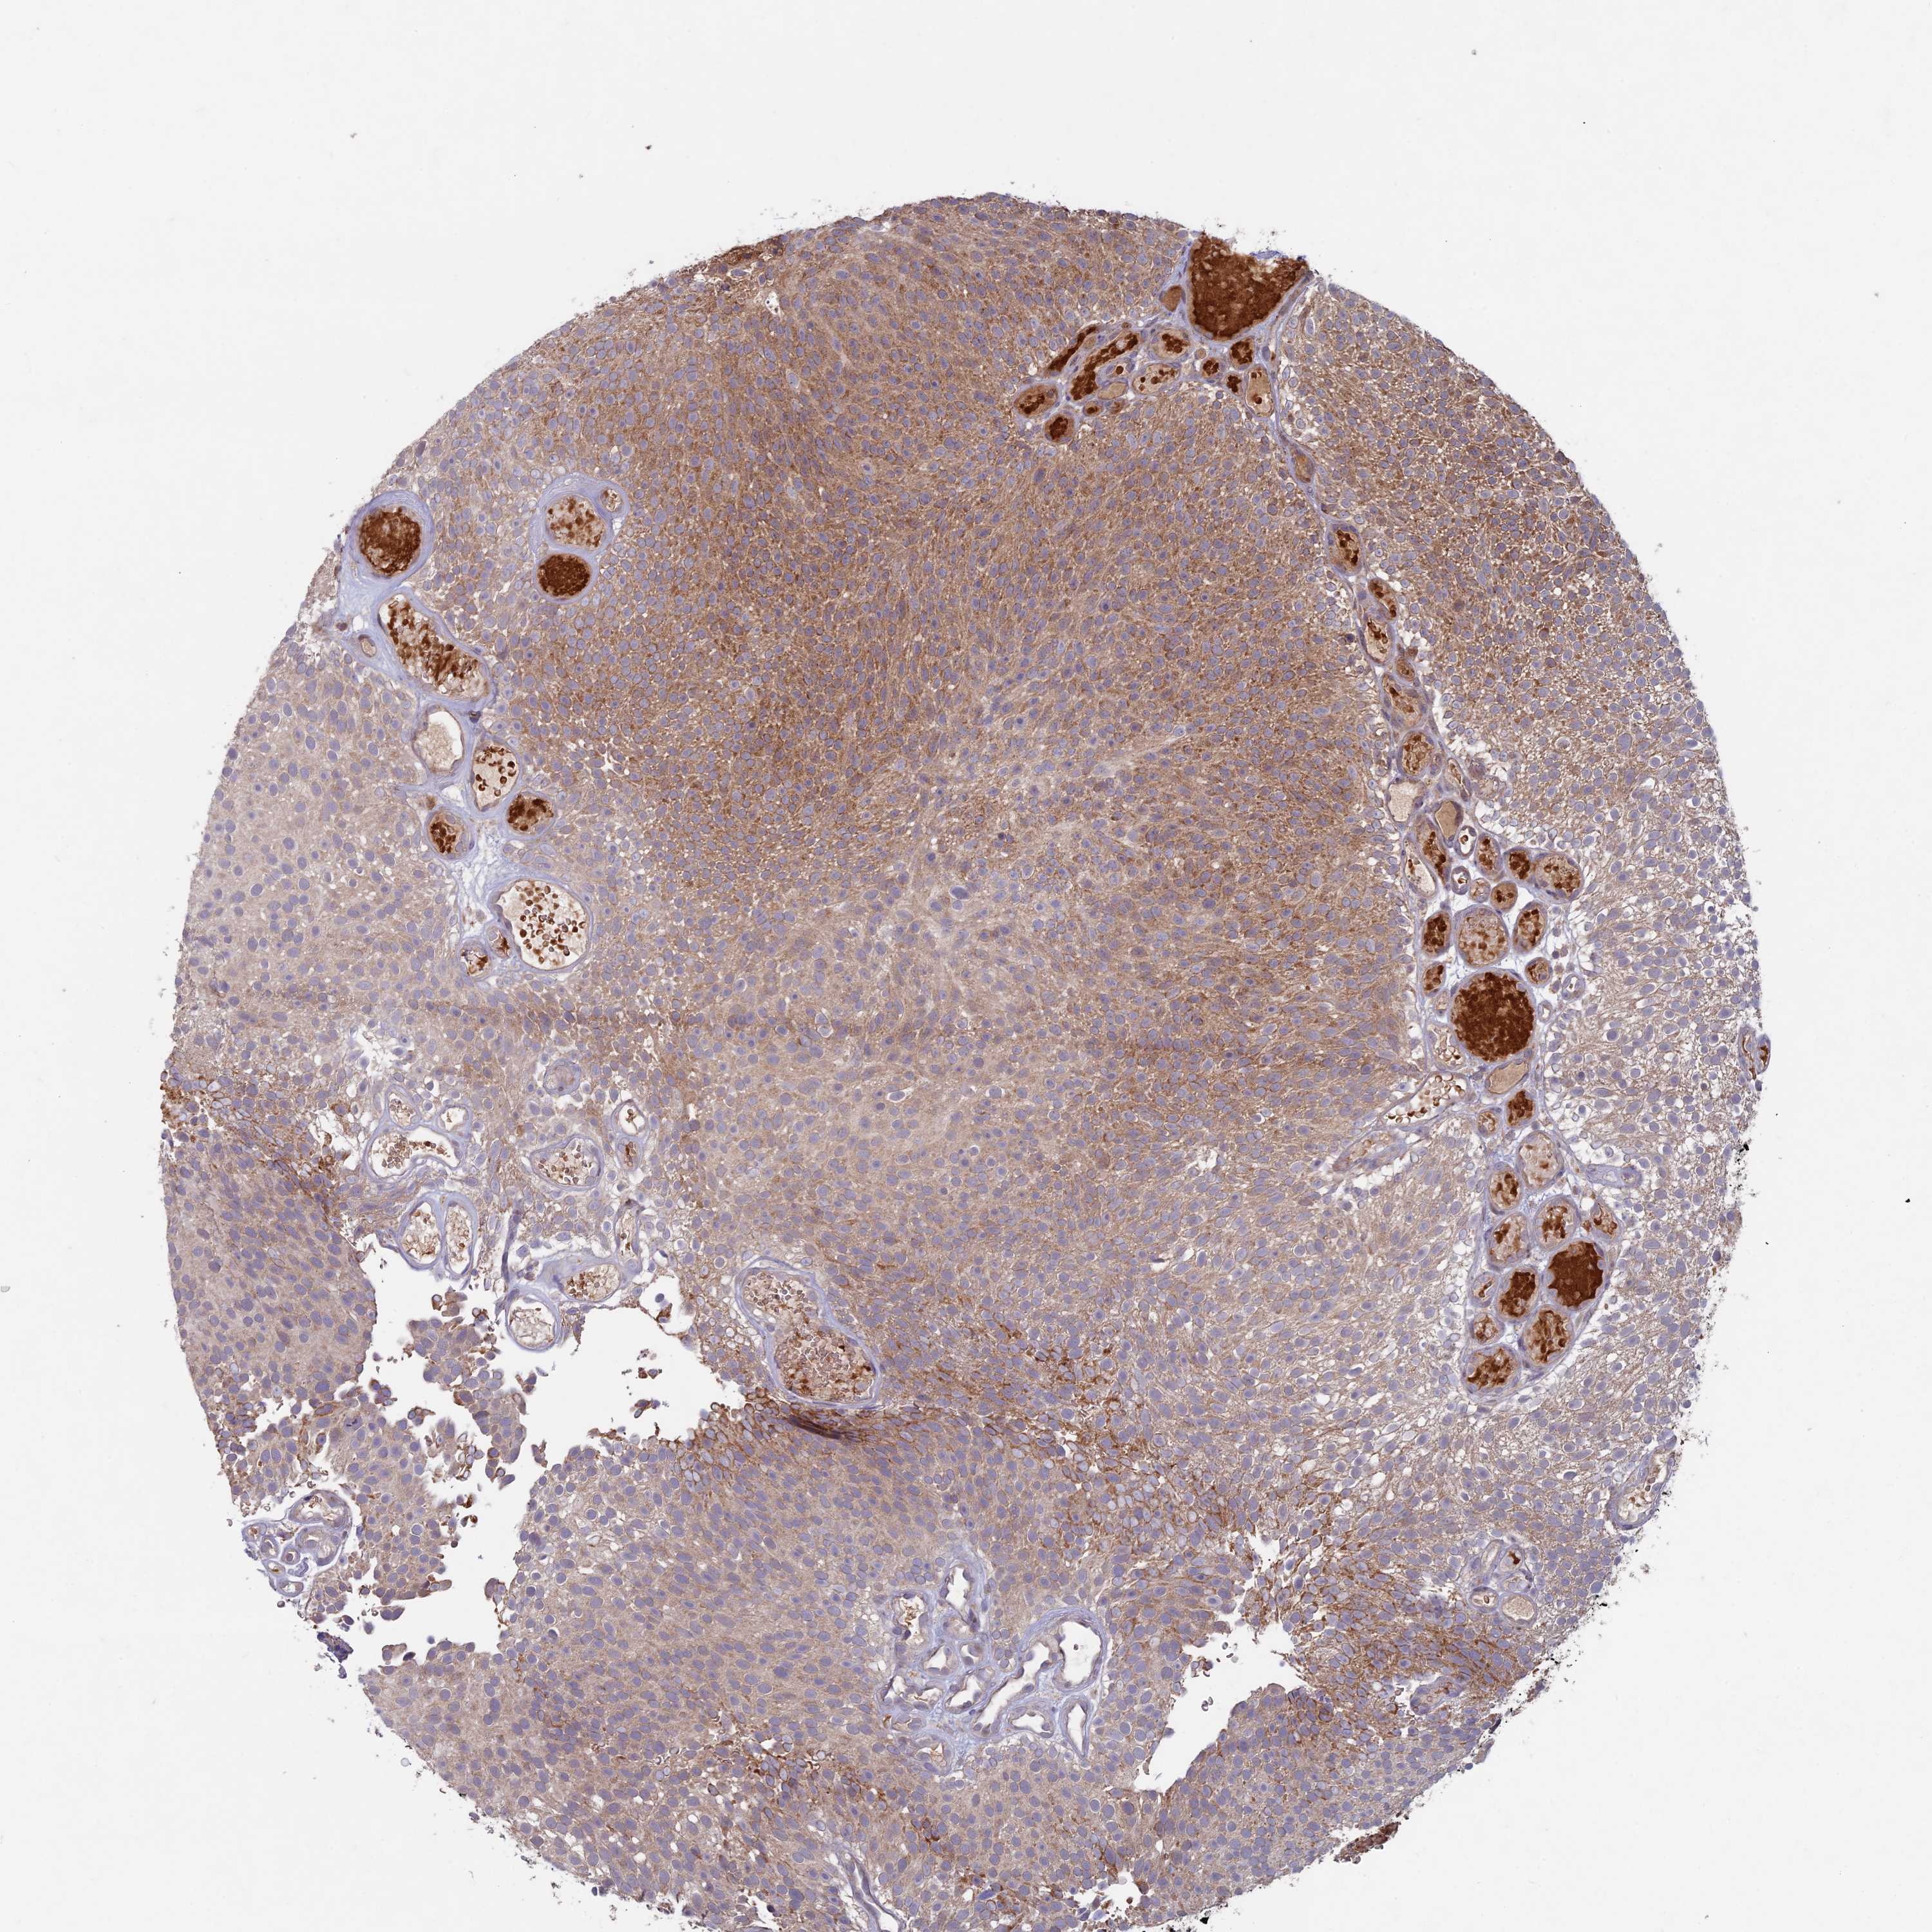

UROTHELIAL CANCER - Protein expressioni

A mouse-over function shows sample information and annotation data. Click on an image to view it in a full screen mode. Samples can be filtered based on level of antibody staining by selecting one or several of the following categories: high, medium, low and not detected. The assay and annotation is described here.

Note that samples used for immunohistochemistry by the Human Protein Atlas do not correspond to samples in the TCGA dataset.

Antibody stainingi

Antibody staining in the annotated cell types in the current human tissue is reported as not detected, low, medium, or high, based on conventional immunohistochemistry profiling in selected tissues. This score is based on the combination of the staining intensity and fraction of stained cells.

Each image is clickable and will lead to virtual microscopy that enables deeper exploration of all samples and also displays staining intensity scores, fraction scores and subcellular localization as well as patient and tissue information for each sample.

Antibody HPA039683

Antibody HPA040776

Urothelial carcinoma, High grade

Urothelial carcinoma, Low grade